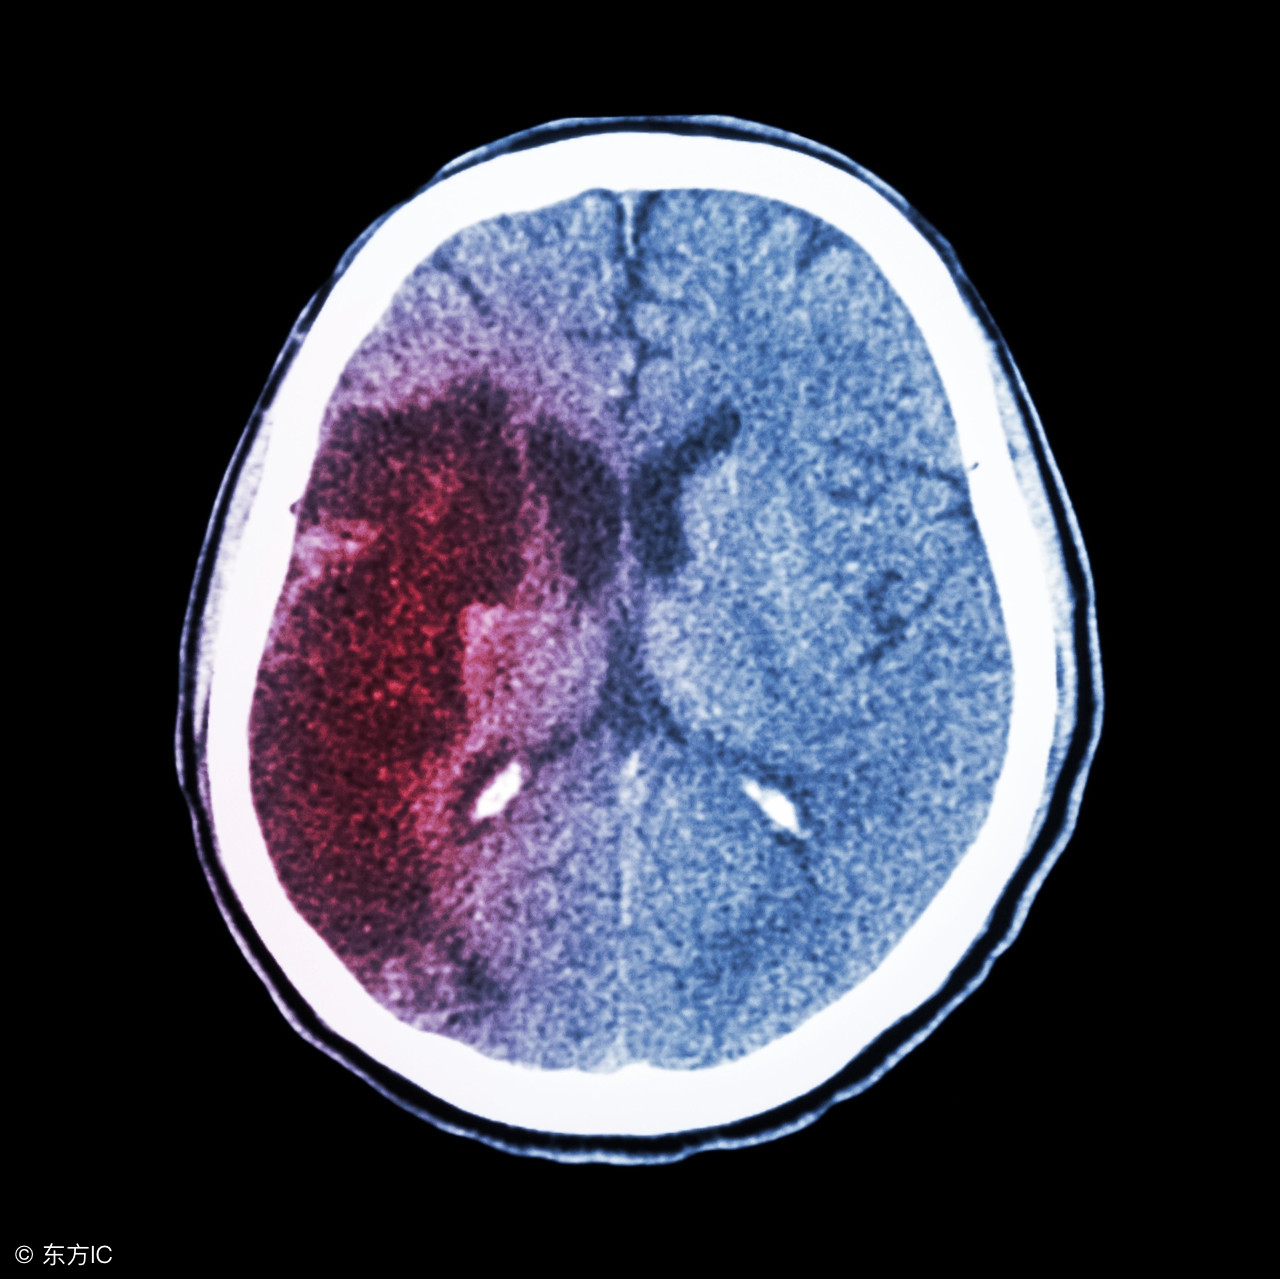

高血压脑出血手术后的饮食